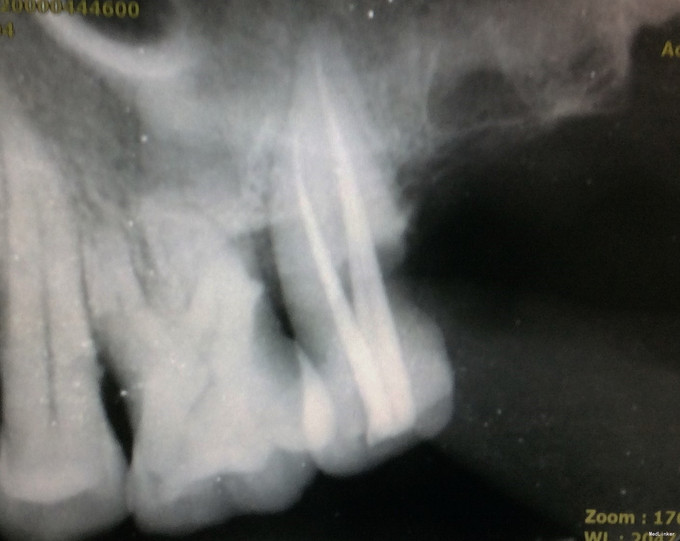

诊断:27牙慢性牙髓炎 治疗方案: 1、27牙根管治疗+充填修复+冠修复 2、27牙显微根尖外科手术 3、27牙干髓术 4、46牙择期治疗 经与患者详细介绍每种治疗方案的治疗经过、费用及预后,患者选择方案1。 治疗经过: 初诊:因患者咽反射强,无法上橡皮障。27牙涡轮机去龋,未去净龋坏时见穿髓孔,但因髓腔钙化及解剖牙冠长,不能探及明显髓腔结构;ET20清理髓腔内钙化,探及3根管口。其中近颊根根管口探痛明显,封“三聚甲醛”;CAVITON暂封。 首次复诊:27牙去净暂封,根测仪测定根管长度,近颊根19mm,远颊根19mm,腭根20mm;机用镍钛器械Protaper清扩至#2506锥度,腭根清扩至#3504锥度,示尖到位;超声荡洗,次氯酸钠冲洗,纸尖吸干,根管内封氢氧化钙,髓腔置干棉球,CAVITON暂封。 二次复诊:27牙去暂封,去棉球,超声荡洗根管,次氯酸钠冲洗,再次测量根管长度,纸尖吸干,AH糊剂+大锥度牙胶尖封闭根尖段,热牙胶封闭根中上段,拍片示根充到位;腭根预备纤维桩道,冲洗,干燥,粘接#13纤维桩;涂布粘接剂,流体树脂垫底,3M纳米树脂充填修复,调he,抛光。

1、从全景片中可见,该牙龋坏已与髓腔相通,髓腔较为明显。但开髓时发现,髓腔内几乎均钙化,髓腔空间及其狭小。且该牙解剖牙冠长,且为上颌最后颗磨牙,若对牙体解剖没有足够地掌握,没有充足的经验,非常容易开髓开偏或找不到根管口,或有遗漏根管,因为近颊根根管口被钙化的牙体组织完全覆盖。此种情况下,若使用涡轮机企图去除牙体组织后寻找根管口非常困难,若在显微镜下使用超声则为最佳选择。 2、该牙虽然冠的上部牙体组织无去坏,但仍然去除掉了。虽然对牙齿的创伤较大,但若不去除这些无机釉,一来可能龋坏无法去除干净,二来抗力形不足,容易折断。 3、该牙髓腔内牙髓完全坏死,但各个根管内均有较好牙髓活力。说明牙髓的坏死是一个渐进的过程,即便是髓腔及根管开始钙化,牙髓也可有活力。